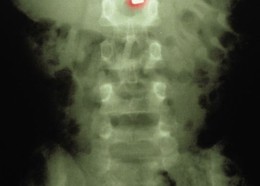

Чудни ренгенски снимки